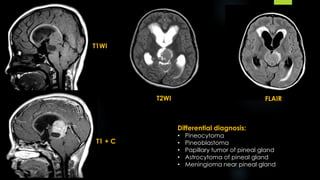

T1WI

T2WI

T1 + C

Differential diagnosis:

 Pineocytoma

 Pineal papillary tumor

 Germinoma

 Astrocytoma of pineal gland

 Pineal cyst

T2WI FLAIR

• Pineocytoma

• Pineoblastoma

• Papillary tumor of pineal gland

• Astrocytoma of pineal gland

• Meningioma near pineal gland